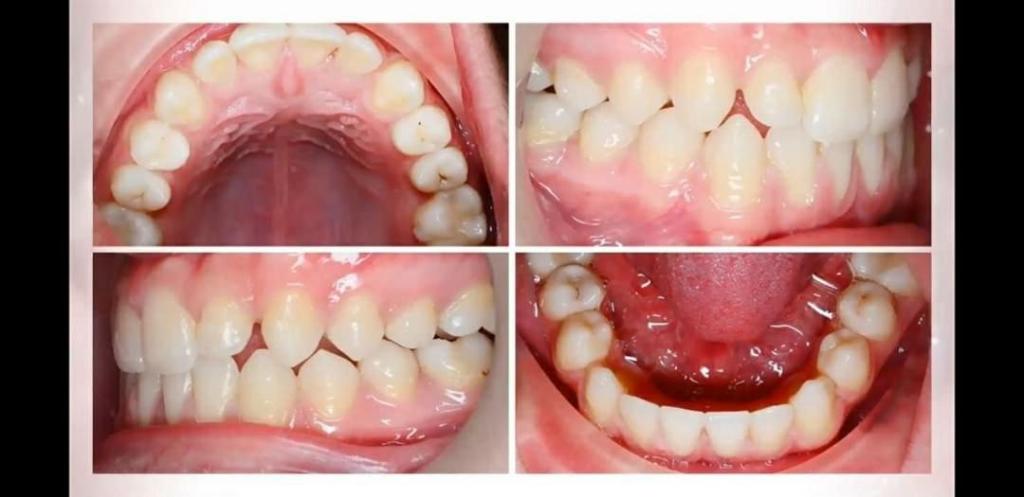

(الميكانيكية الحيوية والسريرية لتطبيقات معالجات تقويم الاسنان الشفاف)قدمت من خلالها الدكتورة شرح مفصل عن آلية واهمية وفائدة هذا الجهاز الجديد والمستخدم في علاج تقويم الاسنان. مستعرضة بامثلة لحالات مرضية تم علاجها باستخدام هذا الجهاز.